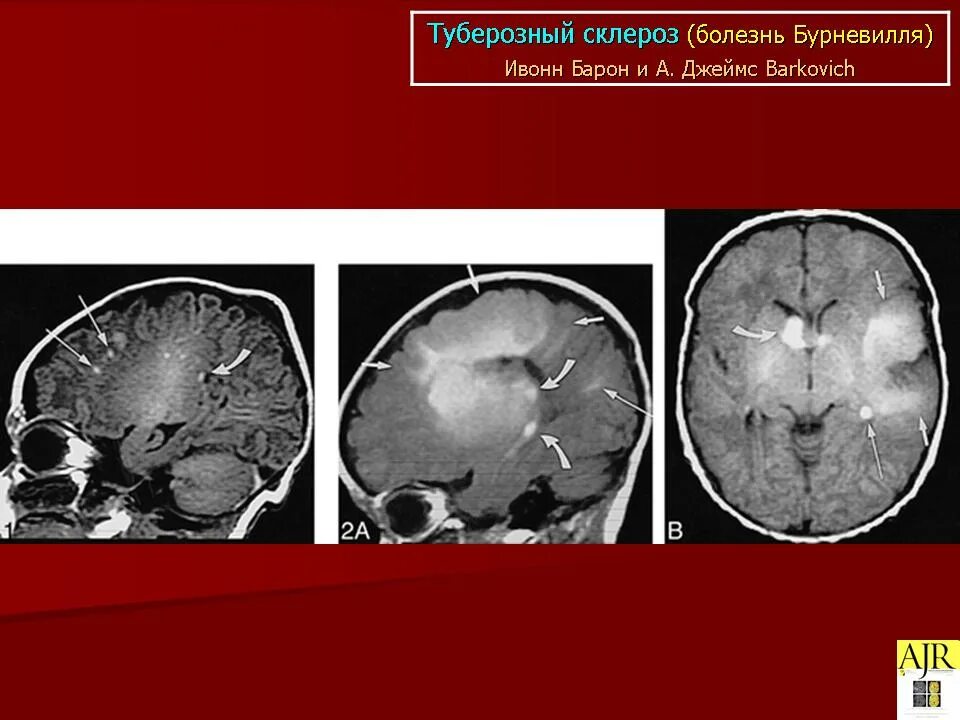

Туберкулезный склероз